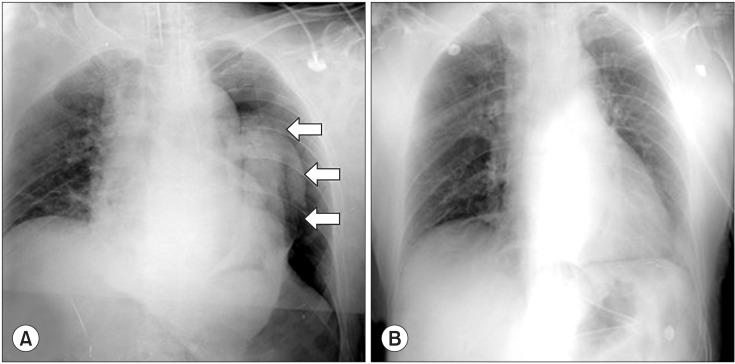

During laparoscopic surgery, carbon dioxide (CO2) pneumothorax can develop due to a congenital defect in the diaphragm. We present a case of a spontaneous massive left-sided pneumothorax that occurred during laparoscopy-assisted gastrectomy, because of an escape of intraperitoneal CO2 gas, under pressure, into the pleural cavity through a congenital defect in the esophageal hiatus of the left diaphragm. This was confirmed on intraoperative chest radiography and laparoscopic inspection. This CO2 pneumothorax caused tolerable hemodynamic and respiratory consequences, and was rapidly reversible after release of the pneumoperitoneum. Thus, a conservative approach was adopted, and the remainder of the surgery was completed, laparoscopically. Due to the high solubility of CO2 gas and the extra-pulmonary mechanism, CO2 pneumothorax with otherwise hemodynamically stable conditions can be managed by conservative modalities, avoiding unnecessary chest tube insertion or conversion to an open procedure.